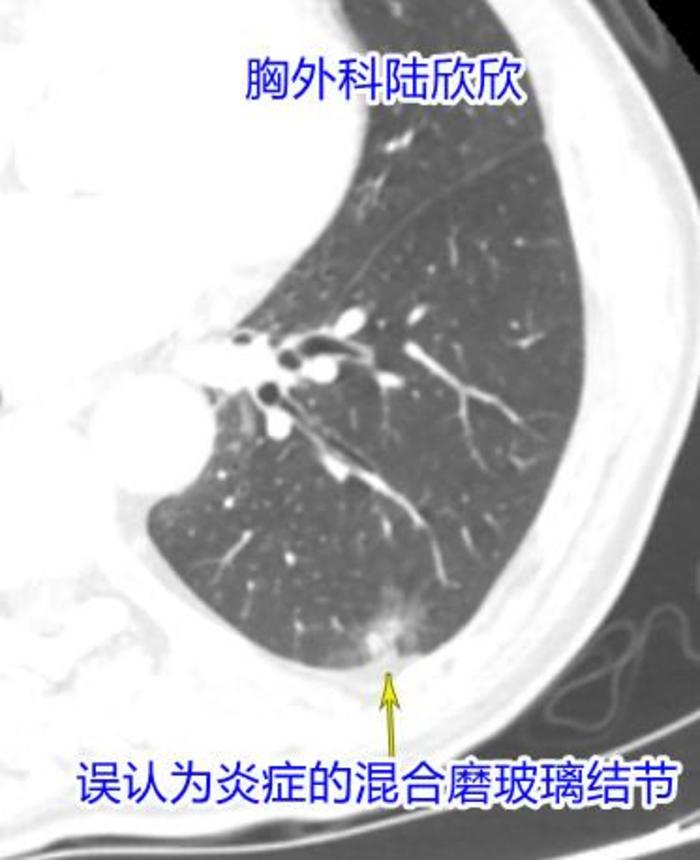

我再仔细看看,病人左下肺胸膜下一片阴影。我问了问病人儿子。病人儿子说:“左下肺有肺炎。2年前就挂过水了,但是肺炎没有消掉。”

他们拿出两年前的CT。我对比了一下,说:“2年前这片阴影大约14×8毫米,现在这片阴影增大到22×15毫米.阴影明显增大,这个阴影不是肺炎,是个混合磨玻璃结节,比较大,也要手术治疗。”